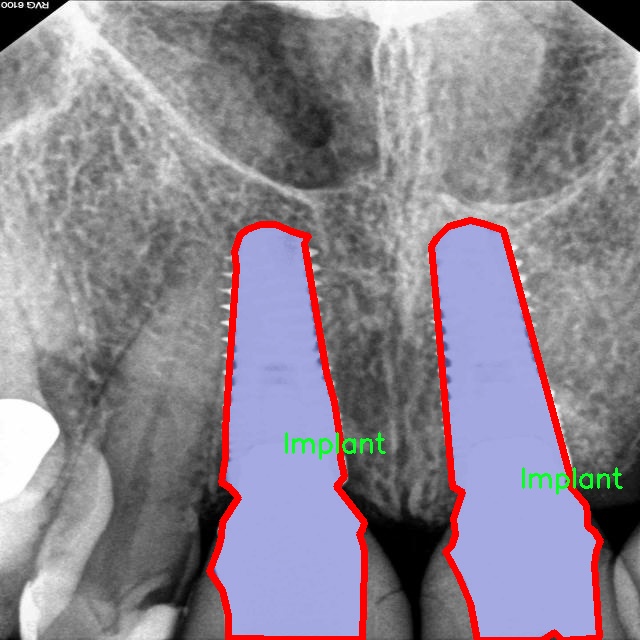

图片效果

在本研究中,我们采用了名为“rvg-v1”的数据集,以支持对牙片牙齿病变图像分割系统的训练,旨在改进YOLOv8-seg模型的性能。该数据集专门为牙科影像分析而设计,涵盖了多种常见的牙齿病变类型,具有重要的临床应用价值。数据集的类别数量为18,涵盖了从常见的牙齿病变到复杂的牙科情况,提供了丰富的样本以供深度学习模型进行训练和验证。

“rvg-v1”数据集中的类别包括:脓肿(Abscess)、磨损(Attrition)、骨丧失(Bone loss)、牙石(Calculus)、龋齿(Caries)、牙冠(Crown)、囊肿(Cyst)、填充物(Filling)、骨折线(Fracture line)、分叉(Furcation)、阻生牙(Impacted)、植体(Implant)、神经(Nerve)、根管治疗(Root canal treated)、根片(Root piece)、窦道(Sinus)、未萌出牙(Unerupted)以及一个通用类别(object)。这些类别不仅涵盖了牙齿常见的病变,还包括了一些较为复杂的牙科情况,能够帮助模型更全面地理解和识别牙科影像中的不同病变特征。